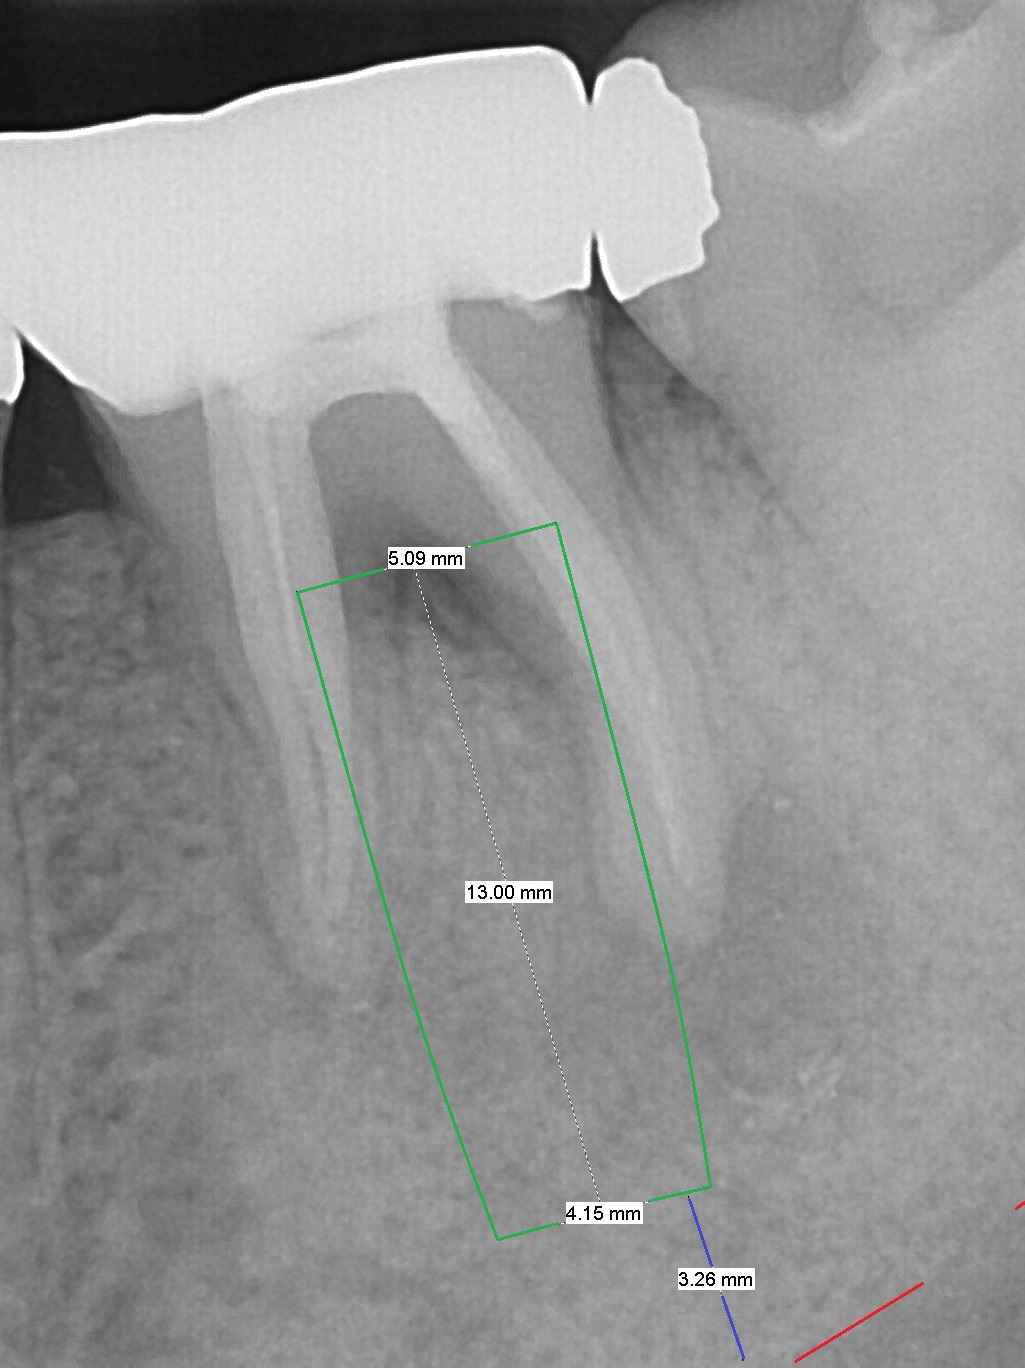

Large Distal Periapical Radiolucency

A 48-year-old woman has had mild discomfort at #19 four years post RCT (Fig.1). It appears that the tooth has 3 roots. The latter should help stabilize an implant placed in the septum (tripods). The affected tooth has large distal periapical radiolucency (Fig,2 *). There is localized swelling at the buccal furca. After debridement, treat the sockets with Clindamycin. Osteotomy will be slightly lingual, since the buccal plate is thinner than the lingual one. In addition, the buccal plate is most likely defective due to furca and periapical lesions. The longest IBS implant is going to be chosen unless the implant has to be placed deep due to furca destruction. In fact the patient has the tooth extracted in other office with socket preservation.